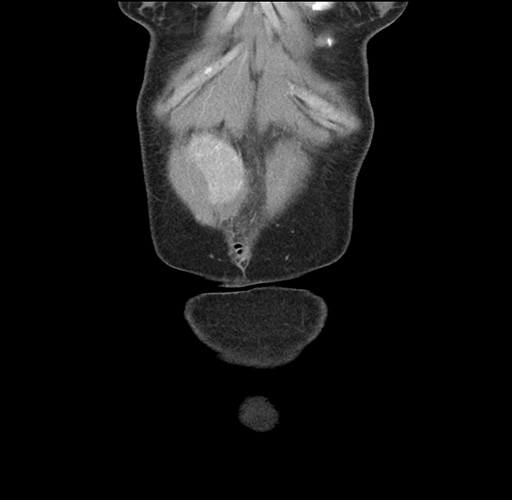

Imaging Analysis

Look through the patient's CT scan to identify any areas of concern for the necessary procedure.

Based on your CT findings, which issue(s) would give reason for "planned slowing down moment(s)" in this case?

Considering a standard left lateral sectionectomy procedure, what step(s) of the operation would you do differently in this case ?